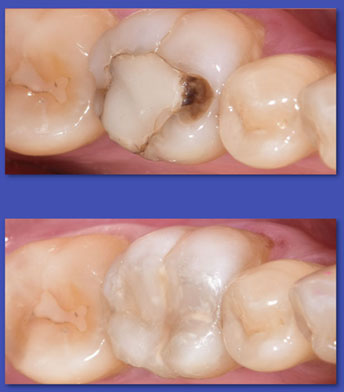

1.  OPERATORIA DENTAL

La Operatoria Dental se dedica a la restauración de los dientes dañados en forma parcial producto de caries, traumatismos  y otras lesiones no cariosas (atrición, abrasión, erosión, hipoplasias de esmalte, etc.). Hoy en día estas restauraciones se realizan en material de resina llamados “composite” que imitan el color del diente y han dejado casi obsoletas a las restauraciones metálicas y amalgamas.

ANTES

DESPUÉS